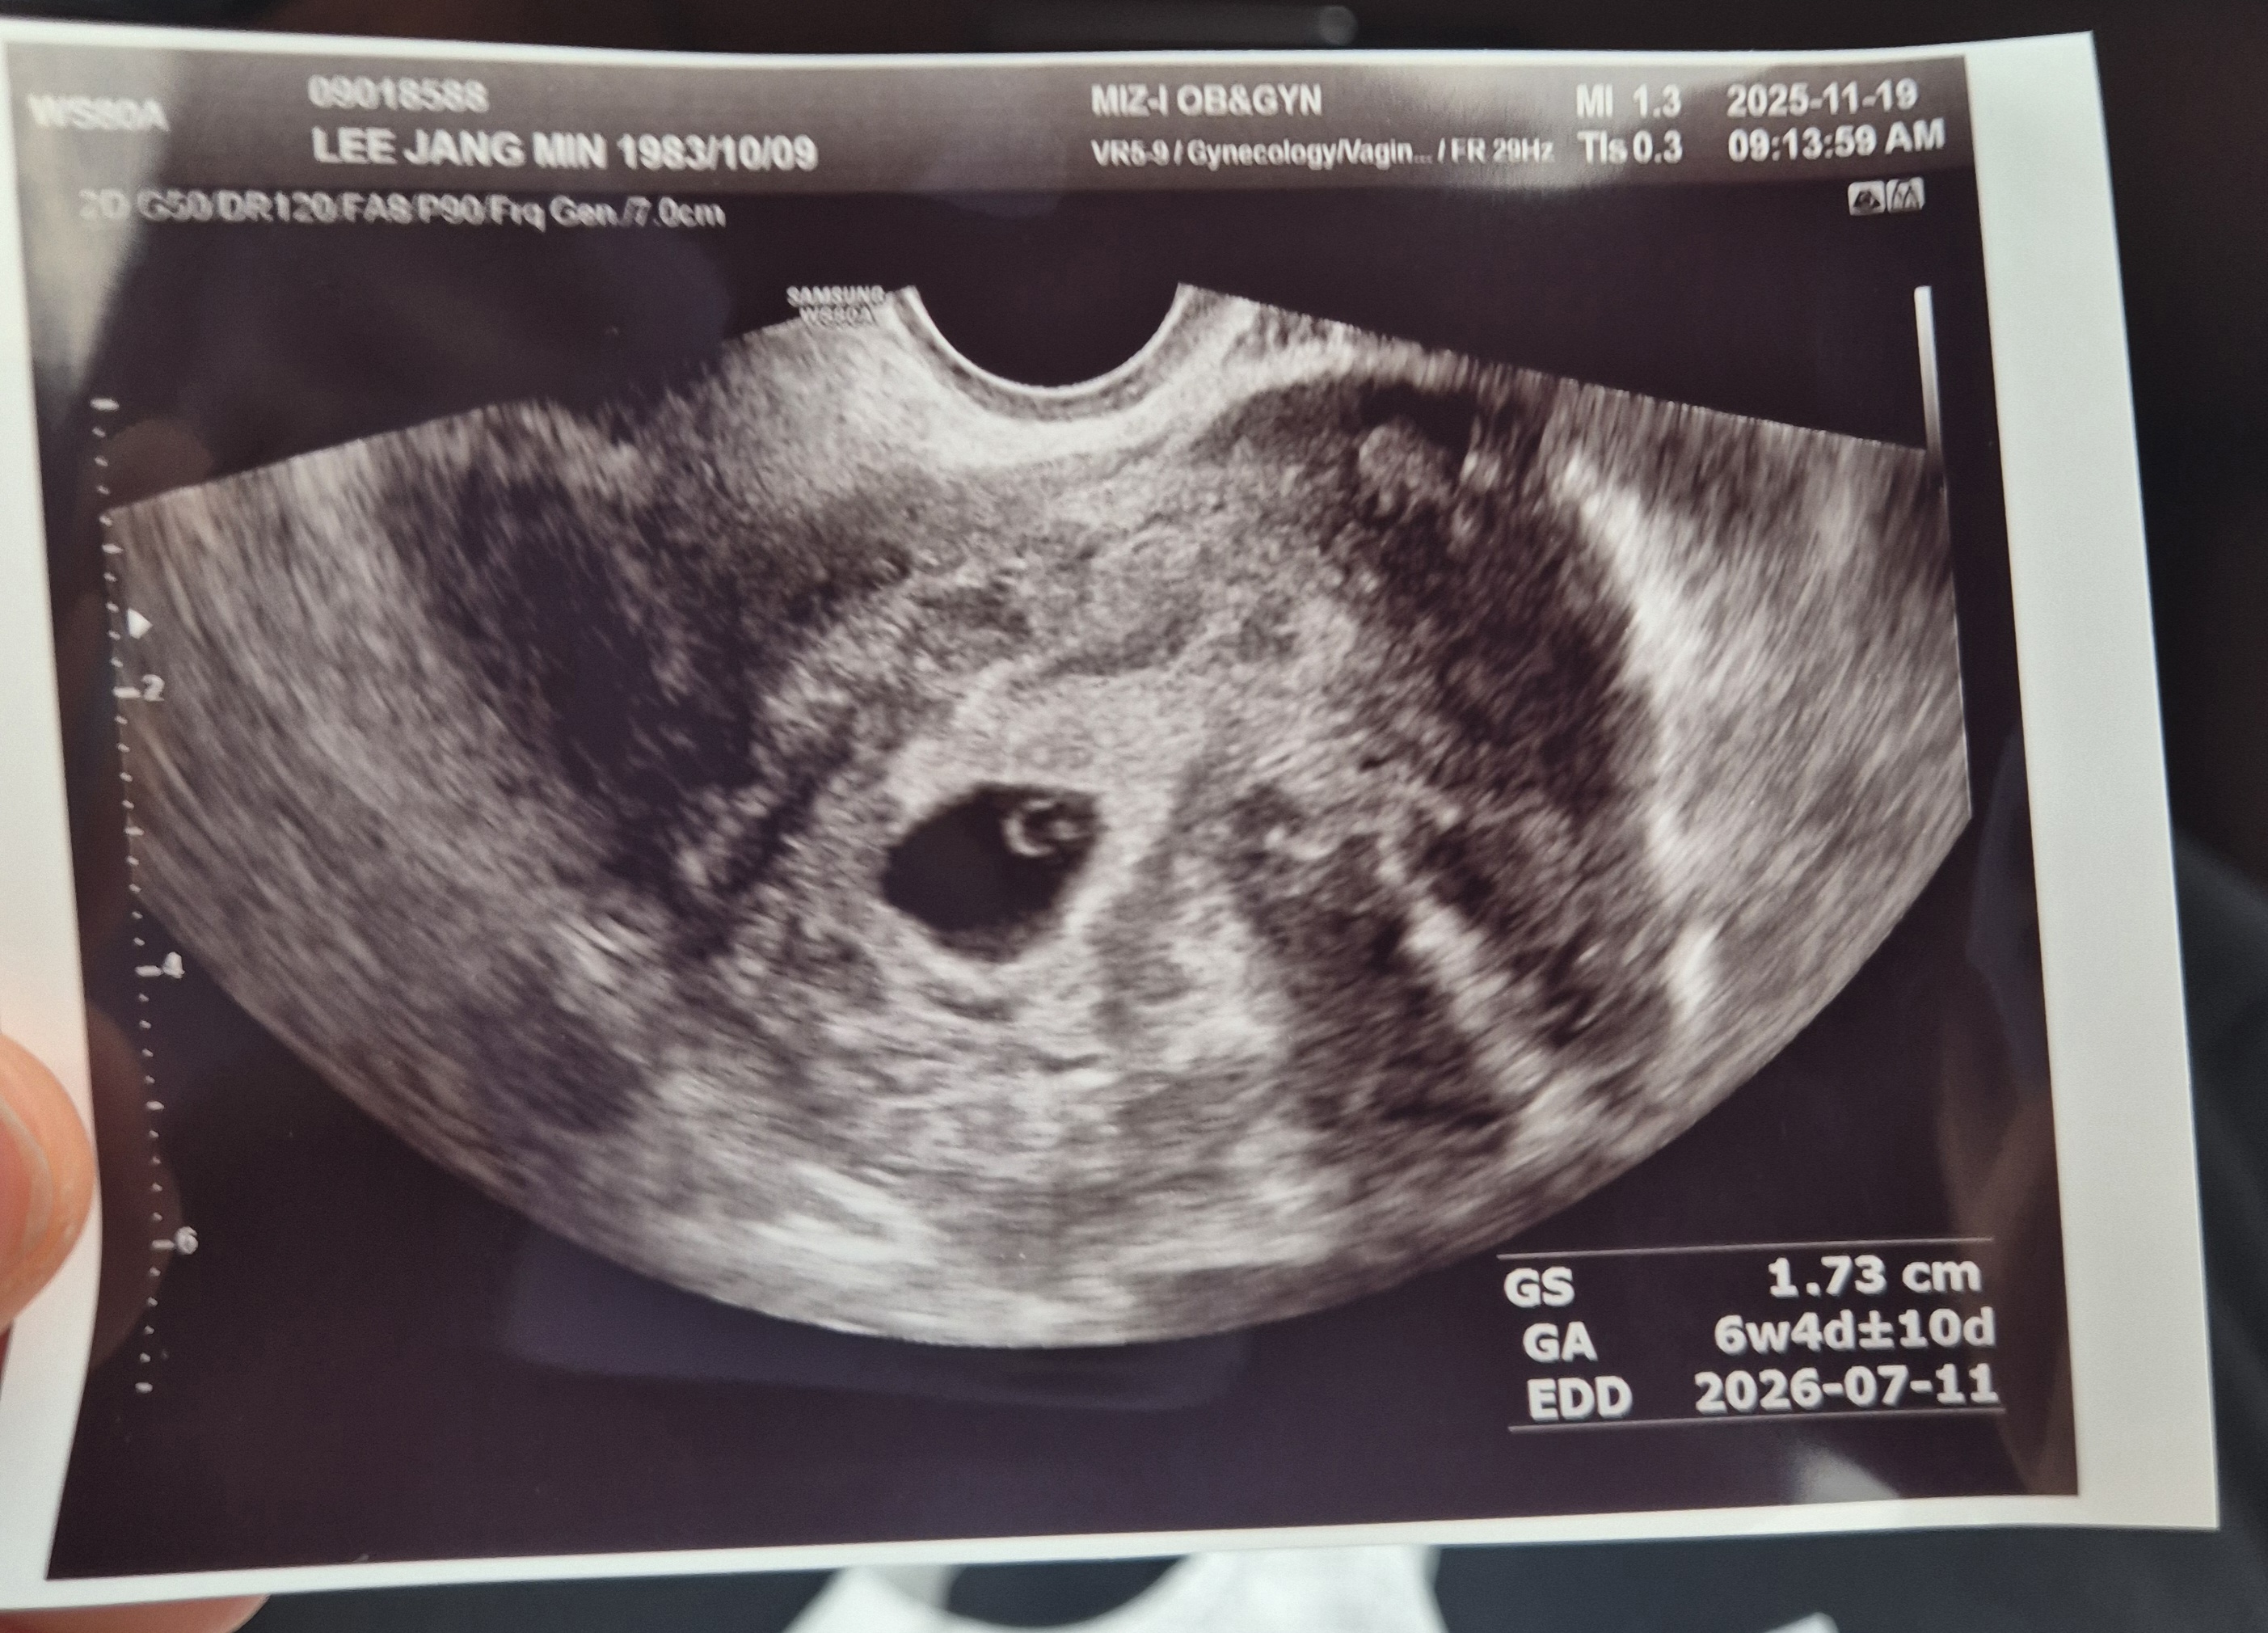

7주차인데심장소리못듣고왔어요

오늘병원갔다왔는데 태아크기도안나오고 심장소리도못들었어요 일주일있다다시보자고아직정확하지않는다고하는데 이런경우있으셨나요

슬픈얘기지만 지난 5월말에 7주차 되었을 때 제가 똑같은 상황이었어요 아기집은 큰데 아기가 너무 작고 심장소리가 거의 안들린다 일주일 후에 보자고 했는데 일주일 후에 보니 심장이 멈춰있었고 아기도 더 안커있더라고요 몇일 후에 계류유산으로 제거시술했어요ㅠㅠ 그래도 주수대비 늦게 크는 걸수도 있으니아기믿고 한주 더 기다려 보시져

저도 그런데다가 피까지 나서 주사맞고 약먹고 질정넣고잇어요 심장소리도 못들엇는데 하루하루 너무 불안해요 ㅠㅜ

착상이 늦게 되어서 나오는 주차보다 더 이른 주차일 수 있을거같아요! 일이주 있다가 한번 더 가보세요